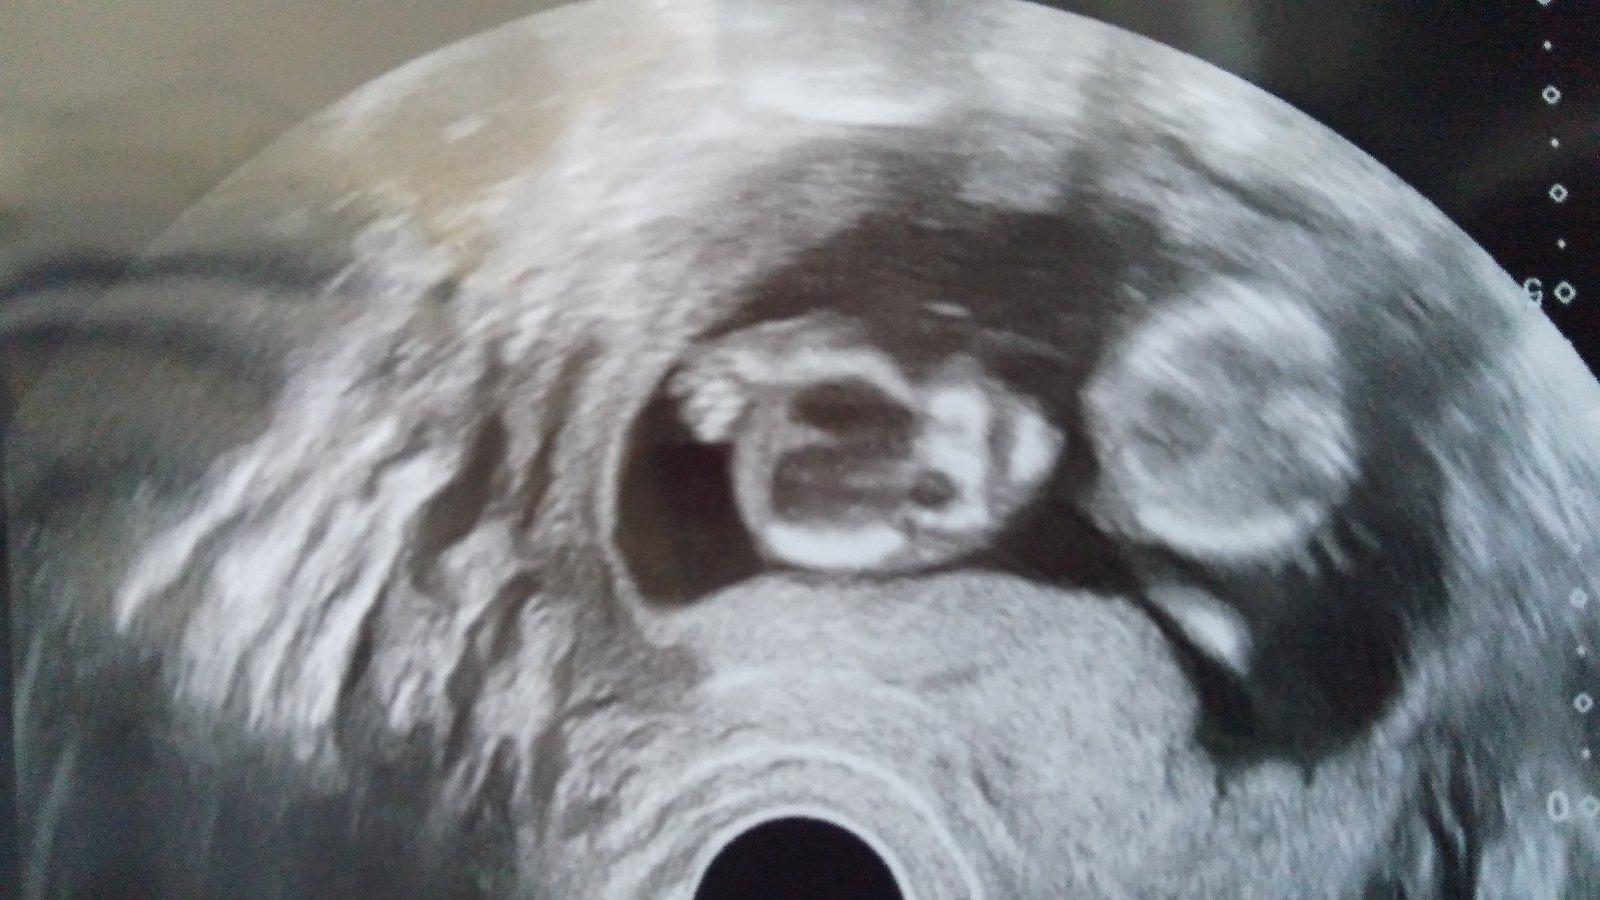

Ahoj holky, díky za vaše zprávičky. Udelaly mi radost. Tak si představte, Verunka říká, ze to naše miminko vypadá jako Olaf 😂😂😂😂 Se tu směju ještě teď.